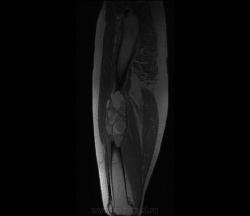

Девочка 9 лет. Родители отмечают, что 2 месяца назад девочка начала предъявлять жалобы на боли в правой пятке. Обследовались, патологии в стопе не нашли. Ребёнок постепенно начал хромать. А несколько дней назад обнаружили припухлость в в/3 бедра. Болей в бедре нет, как ночных, так и дневных. Температура не повышалась. Обратились за помощью - выполнены рентгенограммы, затем - КТ.

Злокачественная опухоль - виден луковичный периостит, инвазивный рост с лизисом кости. Но какая? Вроде бы растет из костного канала. Остеосаркома? Юинг? для этих опухолей структура какая-то больно хрящевая, мягкотканная. Хондросаркома? В таком возрасте? Почему нет клиники злокачественной опухоли кости, прежде всего - болей?

Да, рентгенкартина неоднозначна, конечно, в первую очередь надо исключать зло (Юинга, остеогенную), но не уверена на 100%, что это они, спикул нет, есть луковичный периостит ниже основного очага, но это не критерий злокачественности, вздутие. Был бы возраст помладше, в первую очередь подумала бы о гистиоцитозе или туберкулезе. Еще мысли об аневризмальной кисте и ГКО. Очень хочется узнать результаты гистологии.

Вы правы, коллега, мне тоже видятся уровни. Но если АКК, откуда периостоз? По КТ его оспорить сложно... По скиалогии, локализации наиболее подходит гигантоклеточная опухоль, тем более, что она часто сочетается с вторичной аневризмальной кистой. Но возраст?! хотя, чего сейчас только не бывает...

Чувства смешанные - с одной стороны, появилась немаленькая надежда на доброкачественность процесса. С другой - неужели АКК и ГКО могут ТАК выглядеть???